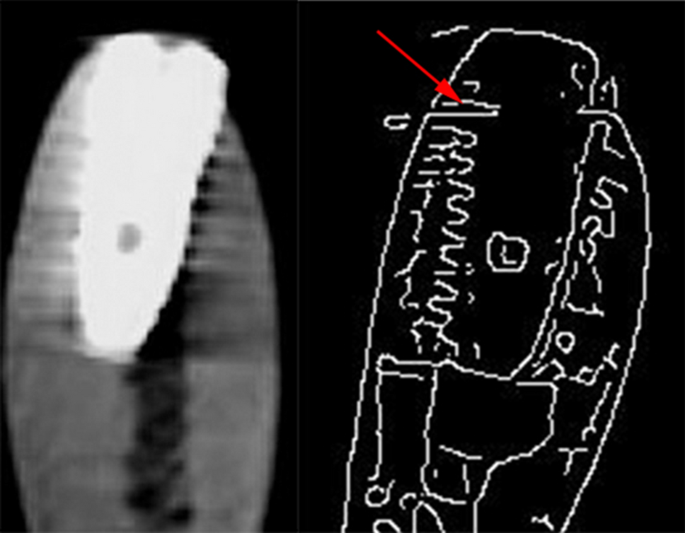

The PPA and OPA images were processed and saved by the Scanora imaging software version 4.3.1 (Digora Optime; Soredex, Tuusula, Finland). CBCT scans were automatically reconstructed (EZ3D-i; Vatech, Yongin, Korea). Cross-sectional views were created for each sample using the “section” tool of the software. Subsequently, the section that best displayed the whole length of the implant was selected and saved. In this way, 4 original-format images (PPA, OPA, CBCT with MAR on, and CBCT with MAR off) were obtained from each implant by the same radiologist who also acquired the radiographs. Afterwards, the images were processed in order to extract their edges. To do so, the Canny edge detection algorithm was used. In this algorithm, firstly, the image noise is removed by a Gaussian filter. Then, by applying a gradient magnitude thresholding technique, the edges of the image are detected. In the present study, based on the observations made by two expert radiologists, different values for the standard deviation of the Gaussian filter and the high and low thresholds were selected for processing the CBCT and periapical images. The aforementioned values were selected by two radiologists at a point where image details were displayed with the greatest fidelity. For the CBCT images the standard deviation of the Gaussian filter was set to 1.2, and 0.07 and 0.028 were used as the high and low thresholds, respectively. For the periapical images, the corresponding values of the parameters were set to 2.0, 0.18, and 0.072, respectively. All image processing stages were performed by codes developed in MATLAB 2018a (Math Works; Natick, MA, USA) computing platform.

Hence, 8 images (4 original and 4 with the applied Canny algorithm) were available as index tests for each sample. Since 24 intact and 24 fractured implants existed, a total number of 384 images were obtained from the study samples. The images were coded with random numbers to be viewed by three observers (two maxillofacial radiologists and a periodontist) who were totally unaware of the condition of the samples. Random numbers ensured that no bias occurred during the image obsevations. The observers were asked to record their diagnoses regarding whether each implant was intact or fractured (Figs. 2 and 3).

Computer-aided systems are gaining popularity in medical and dental imaging diagnosis. These techniques could be applied to nearly all types of radiographic images to enhance the accuracy and feasibility of different diagnostic tasks37. A unique feature of the present study was the application of an auto-edge detection algorithm, i.e. the Canny algorithm for identification of the simulated implant fractures. Canny edge detection algorithm is an accurate tool for defining the outline features of an object as well as detecting sharp intensity changes in an image. The algorithm works in MATLAB computing platform and has been used in medical imaging for expressing bone changes of osteoporosis and also artifact quantification in CT images22,23. Canny edge detection algorithm benefits from being less sensitive to sources of image noise including gray level inhomogeneity caused by exposure conditions, patient’s position, and environmental temperature38. Since it has the capability of defining the intensity changes and sharp edges of an image with the least amount of noise, we decided to apply it on the radiographic images to determine whether it enhances the accuracy of the radiographic images for implant fracture diagnosis. Three parameters of the Canny algorithm including standard deviation of the Gaussian filter, high, and low sensitivity thresholds can be adjusted manually by the operator. In this study, two expert radiologists who were not among the observers defined the aforementioned parameters in the CBCT and periapical images by testing different values until they both reached a point with the least amount of noise and finest image details.